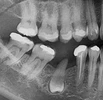

تسوس الأسنان

أكياس الفك

علاج الزرع السني